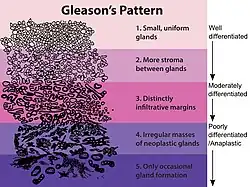

Die Einteilung umfasst ursprünglich fünf Grade, welche sowohl die Form, als auch die Anordnung der Drüsen beschreibt. Die Grade 1 und 2 sollen jedoch nicht mehr vergeben werden.[2] Grad 3 beschreibt kleine ungleichmäßige Drüsen, Grad 5 beschreibt die am schlechtesten differenzierten Tumoren, deren Wachstumsmuster fast jede Ähnlichkeit mit normalem Prostatagewebe verloren haben, Grad 4 liegt dazwischen.[3]

-

-